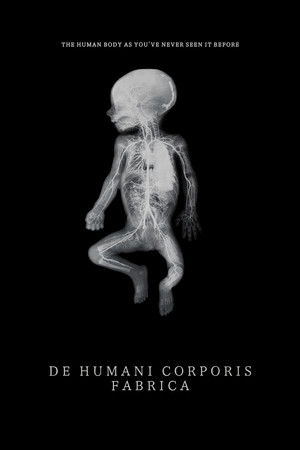

De humani corporis fabrica

(2023)Overview

An extraordinary adventure through the interior of the human body; or the discovery of an alien landscape of unprecedented beauty.